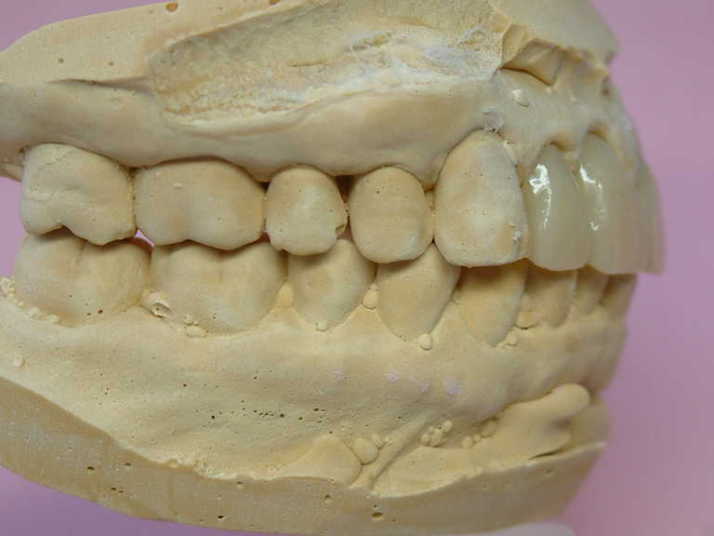

下顎前歯切端を内側に削って頂いた所 |

補綴物物 完成

患者さんから「出っ歯にならないよに!」

と再度念を押されたので

出来る限り内側に入れて製作しました。

模型上では、1.1下部孤形空隙が広いように

見えますが、歯肉模型にて調整して

歯肉を圧迫せず、息が漏れることが無いように

調整しました |